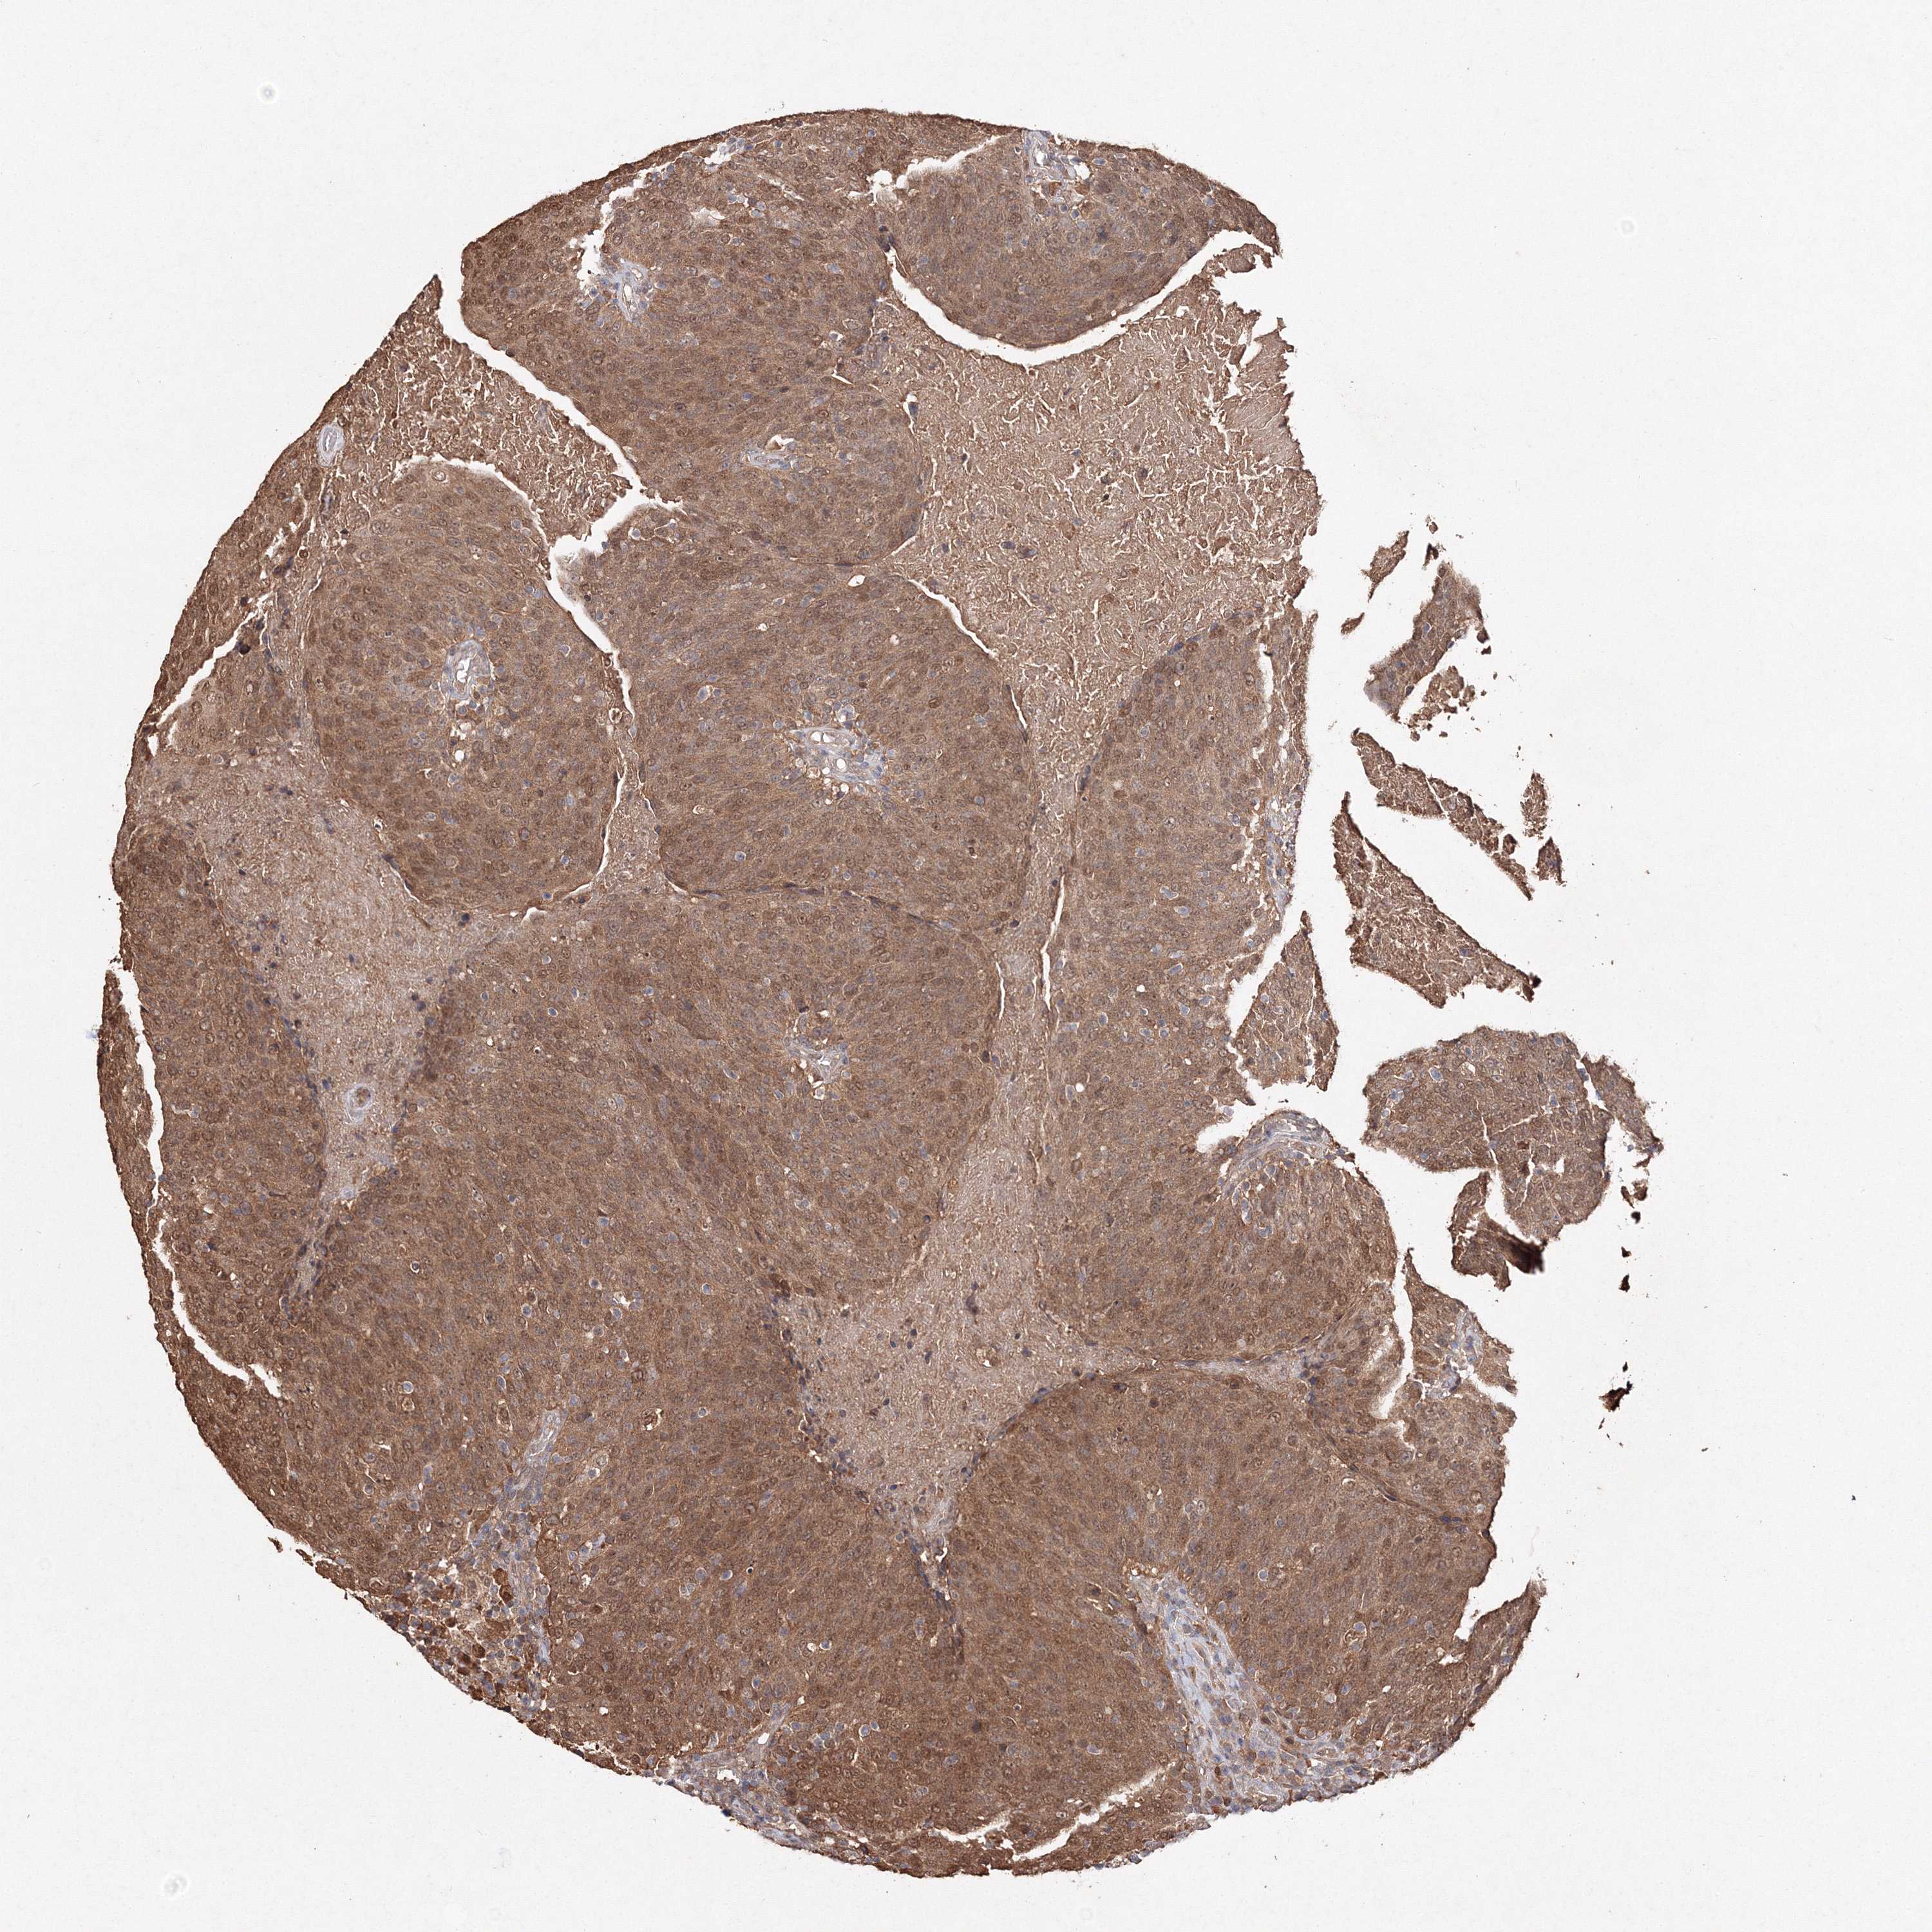

HEAD AND NECK CANCER - Protein expressioni

A mouse-over function shows sample information and annotation data. Click on an image to view it in a full screen mode. Samples can be filtered based on level of antibody staining by selecting one or several of the following categories: high, medium, low and not detected. The assay and annotation is described here.

Antibody stainingi

Antibody staining in the annotated cell types in the current human tissue is reported as not detected, low, medium, or high, based on conventional immunohistochemistry profiling in selected tissues. This score is based on the combination of the staining intensity and fraction of stained cells.

Each image is clickable and will lead to virtual microscopy that enables deeper exploration of all samples and also displays staining intensity scores, fraction scores and subcellular localization as well as patient and tissue information for each sample.

Antibody HPA042745

Squamous cell carcinoma, NOS